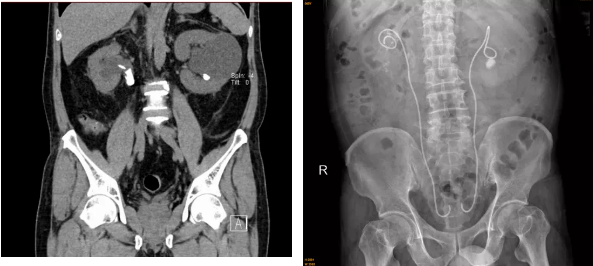

原来在5月初,69岁的郭叔因左侧腰痛伴少尿4天,自行服药效果不佳来到我院。医院检查时发现,其双侧输尿管结石梗阻,血肌酐水平超出正常高限十多倍,达到1375.8μmol/L。(正常范围:44μmol/L-133μmol/L,血肌酐的升高就说明出现了肾功能不全)。

泌尿外科林茂副主任医师、张俊文主治医师考虑患者系泌尿系结石阻塞尿路引起的急性肾衰竭。先为患者行右肾造瘘术解除梗阻恢复,随后在其右侧输尿管上段开展狭窄扩张术、右侧输尿管镜下碎石取石术和双侧输尿管“双J”管内置术。

术后,郭叔的尿量逐渐恢复正常,血肌酐指标水平明显下降至200μmol/L左右。